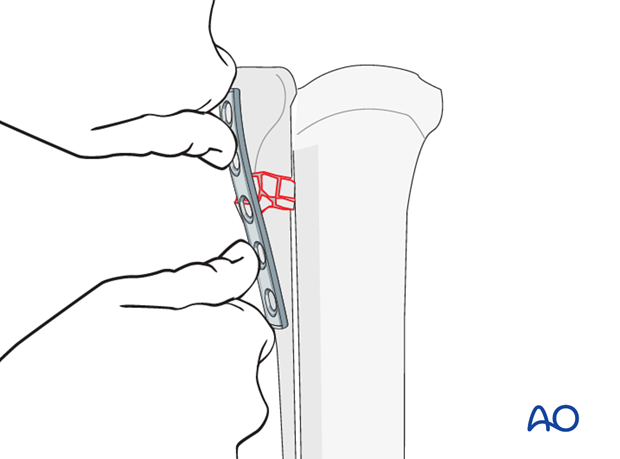

The plate is positioned on the palmaro/plantaro-latero/medial side of the splint bone. Special care must be taken to the orientation and location of the plate, so that at least two screws can be inserted on each side of the fractured zone. In the distal part, the screws need to be very short to avoid protrusion into the third metacarpal/-tarsal bone.

Minimal contouring of the plate is necessary to match the contours of the proximal splint bone. No torsional adjustments of the plate are required. The plate can be bent with either the bending pliers or the bending press.

Normally, the first reduction can be achieved by digital pressure on the fragments.

The plate is then applied to the proximal fragment with one screw applying routine technique.

Before the second screw is inserted correct positioning of the plate is assured. Plate orientation cannot be changed after insertion of the second screw.